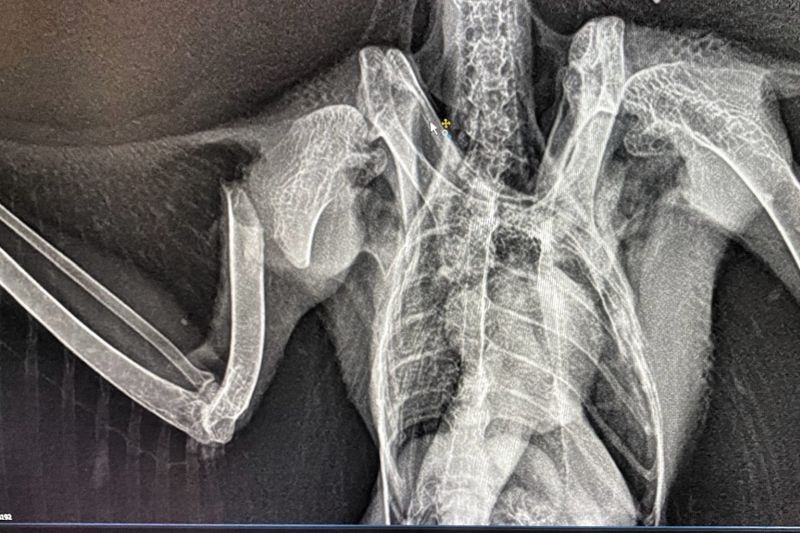

In unserer modernen, verbauten Welt ist der Luftraum kein sicherer Ort mehr. Was für uns Fortschritt und Infrastruktur bedeutet, wird für Eulen, Greif- und Wasservögel oft zur tödlichen Falle. Eine Wildvogelstation ist weit mehr als nur ein Ort für die Aufzucht flauschiger Küken – sie ist ein Lazarett an der vordersten Front.

Die Verletzungen, die wir täglich behandeln, sind keine Unfälle der Natur. Sie sind die direkten Folgen unseres menschlichen Wirkens:

• Infrastruktur-Opfer: Anflüge gegen Hochspannungsleitungen und die rotierenden Schaufeln von Windrädern sorgen für schwerste Traumata und Amputationen

• Tödliche Barrieren: Stacheldraht zerschneidet Schwingen; Glasfronten und der Straßenverkehr führen zu massiven inneren Verletzungen und Knochenbrüchen.

Die folgenden Bilder zeigen ungeschönt den Alltag in der medizinischen Notversorgung. Sie sehen Blut, offene Wunden und chirurgische Eingriffe. Das ist die notwendige, harte Arbeit hinter den Kulissen. Wir kämpfen um jedes Leben – mit Skalpell, Verband und fachmedizinischer Expertise –, um die Fehler wiedergutzumachen, die unsere Zivilisation verursacht hat.

Die folgenden Aufnahmen sind nichts für schwache Nerven. Sie zeigen Blut, offene Frakturen und den harten Kampf im Operationssaal. Wir zeigen sie bewusst. Denn diese Bilder sind die ungeschönte Antwort auf unsere Art zu leben.

Hinter jedem Foto steht ein Schicksal, ein Kampf und unser unermüdlicher Einsatz, das Unrecht der Zivilisation medizinisch zu korrigieren.